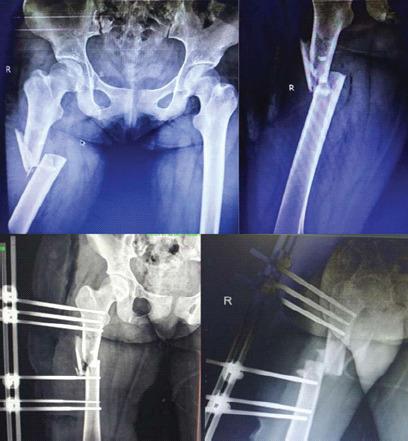

A 25-year-old female patient presented with pain and swelling over the anterolateral aspect of the right thigh after a traumatic road traffic accident 2 days back. On radiological investigation, there was subtrochanteric femur fracture with a butterfly fragment. The patient also had Morel-Lavallee lesion on local ultrasound. Emergency management was done for Morel-Lavallee lesion in the form of percutaneous drainage and compression bandage; fixation was done in the form of external fixator. The wound progressed into complete skin necrosis so external fixator was removed and thorough wound debridement was done. Fracture stabilized with four TENS nails (titanium elastic nail). Removal of the TENS nail and exchange nailing in the form of intramedullary interlocking nail was performed after complete soft-tissue healing. Bony union seen at the fracture site clinically and radiologically at 3-month follow-up.

一名25岁女性患者在2天前发生道路交通事故后,出现右大腿前外侧疼痛和肿胀。经影像学检查,发现股骨转子下骨折并伴有蝶形骨块。患者在局部超声检查中还发现有莫雷尔-拉瓦利损伤。对莫雷尔-拉瓦利损伤进行了急诊处理,采用经皮引流和加压包扎;以外部固定器的形式进行固定。伤口发展为完全皮肤坏死,因此拆除了外部固定器并进行了彻底的伤口清创。用四根TENS钉(钛弹性钉)使骨折稳定。在软组织完全愈合后,取出TENS钉并以髓内交锁钉的形式进行更换钉。在3个月的随访中,骨折部位在临床和影像学上均可见骨愈合。